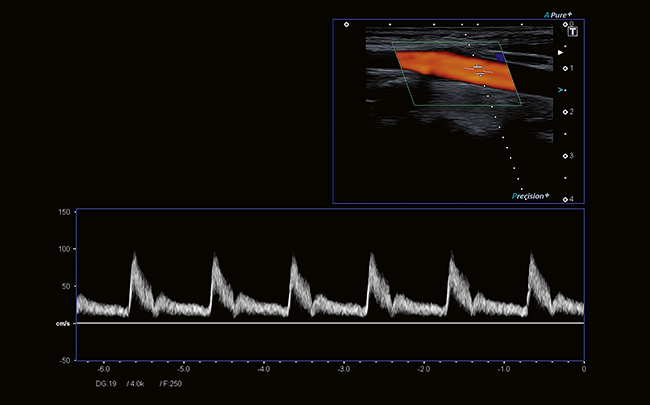

- Импульсно-волновой/постоянно-волновой доплер PWD/CWD

- Цветной доплер CFM

Технология широкополосного преобразователя и обработки сигналов Aplio обеспечивает выдающуюся чувствительность, проникновение и пространственное разрешение для всех доплеровских режимов